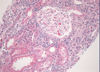

Normal kidney tubules and glomerulus

Interstitial Nephritis; inflammation localized to interstitum primarily, with minor involvement of the tubules

Acute allograft rejection; form of acute interstitial nephritis; where lymphyocytes actually infiltrate the tubules